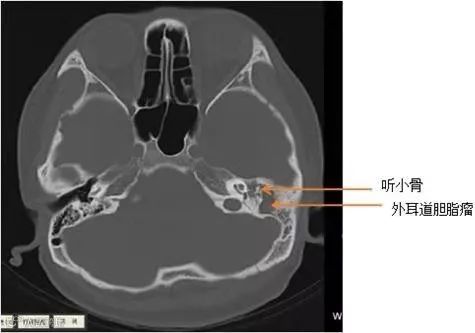

警惕!外耳道胆脂瘤

早期易误诊漏诊